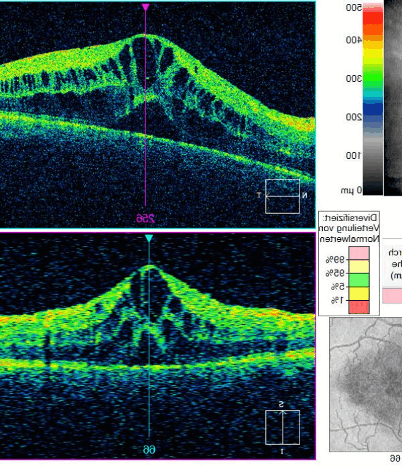

Οφθαλμολογική Εξέταση OCT – (Optical Coherence Tomography)

Η Οπτική τομογραφία συνοχής OCT μοιάζει με αυτή των υπερήχων, με τη διαφορά ότι αντί για ηχητικό κύμα χρησιμοποιεί μονοχρωματική δέσμη φωτός. Δεν υπάρχει συνεπώς επιβλαβής ακτινοβολία για τον ασθενή και έτσι μπορεί να επαναλαμβάνεται αρκετές φορές το χρόνο σε περιπτώσεις όπου χρειάζεται συχνή παρακολούθηση, χωρίς να επιβαρύνεται η υγεία του ασθενή.

Η Οπτική Τομογραφία Συνοχής – OCT είναι χρήσιμη για τη διάγνωση πάρα πολλών παθήσεων του αμφιβληστροειδούς και της ωχράς κηλίδας. Ενδεικτικά, αναφέρονται οι πιο συχνές:

– Ηλικιακή εκφύλιση ωχράς κηλίδας

– Διαβητική αμφιβληστροειδοπάθεια

– Οίδημα ωχράς κηλίδας

– Επαμφιβληστροειδική μεμβράνη

– Οπή ωχράς κηλίδας

– Κεντρική Ορώδης Χοριοαμφιβληστροειδίτιδα κα.

Σημαντικός είναι ο ρόλος της Οπτικής Τομογραφίας Συνοχής – OCT και στην παρακολούθηση του γλαυκώματος. Επιτρέπει την χαρτογράφηση του οπτικού νεύρου και την παρακολούθηση στο χρόνο των μεταβολών του πάχους του αλλά και της κοίλανσης της οπτικής θηλής. Επιτρέπει την πρώιμη διάγνωση του γλαυκώματος, πριν δημιουργηθούν διαταραχές στα οπτικά πεδία.

Τέλος, η Οπτική Τομογραφία Συνοχής – OCT συμβάλλει σημαντικά και στη μελέτη του προσθίου τμήματος του οφθαλμού, του κερατοειδή χιτώνα, της γωνίας του προσθίου θαλάμου και πολλών άλλων δομών.

H εξέταση δεν απαιτεί ιδιαίτερη προετοιμασία από πλευράς ασθενούς. Ο ασθενής τοποθετείται μπροστά στο μηχάνημα (θόλος με κάτοπτρο) και μέσα σε ελάχιστο χρόνο πραγματοποιείται αναλυτική καταγραφή (χαρτογράφηση) της ωχράς κηλίδας.